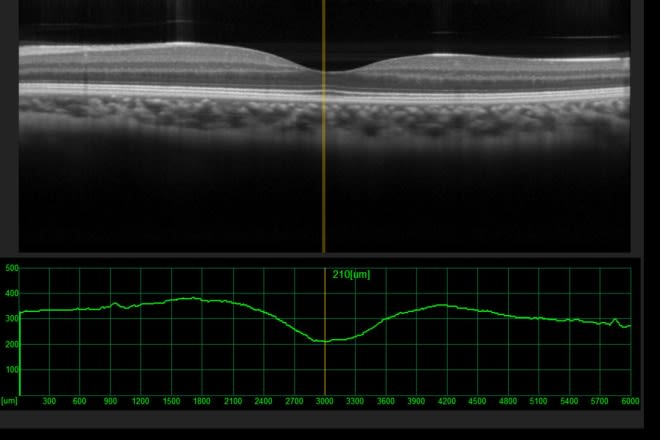

Optical coherence tomography (OCT)

The ophthalmologist uses an OCT machine to scan the inside of your eye for a 3D view of your retina. It helps them see things that shouldn't be there, like the swelling caused by CSCR.

An OCT exam takes 5 to 10 minutes and doesn't hurt.